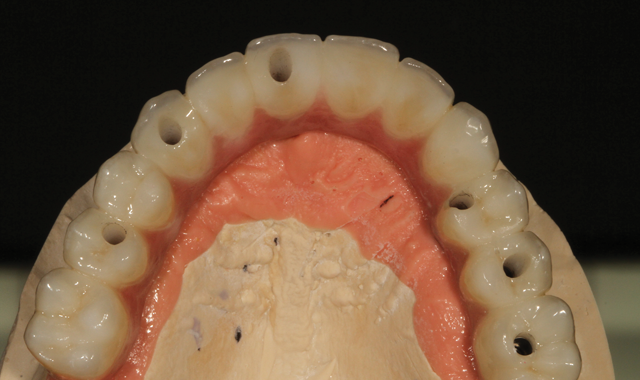

Fig. 12 Occlusion view

In an occlusion view image, the author gives the reader a view of appearance after Lustre Paste application with maximum strength and no porcelain layering involved (Fig. 12).

Fig. 13 Internal implant screws

We can see the internal implant screws in the next mirrored image (Fig. 13), not previously visible.